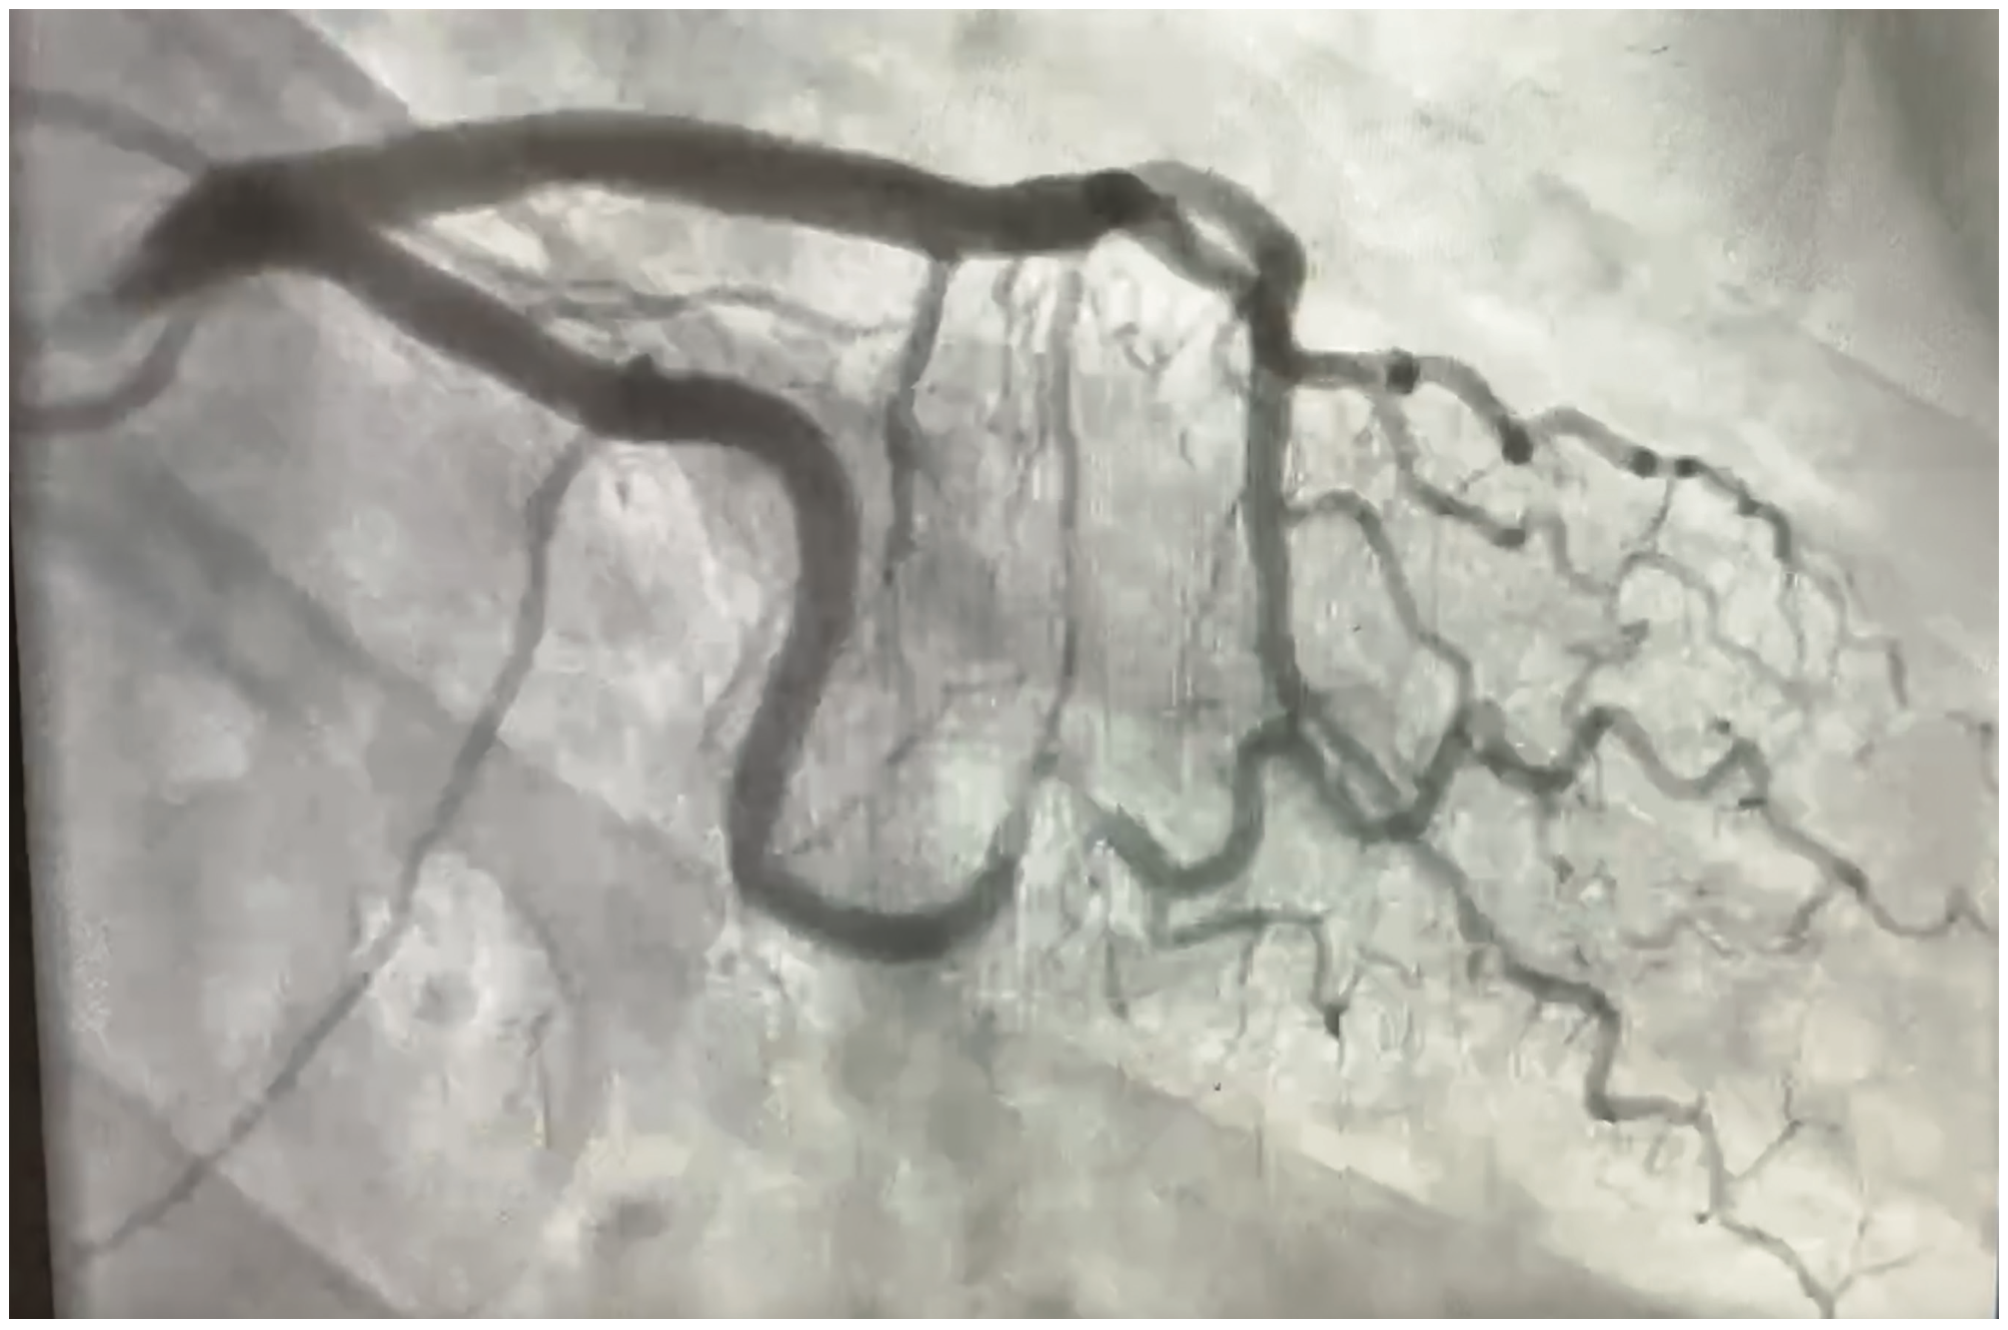

A 54-year-old female presented with acute onset of typical substernal chest pain and was hemodynamically stable. A coronary angiogram (Figure 1/Videos 1-2) showed spontaneous coronary artery dissection (SCAD) type 2a in first obtuse marginal artery. The patient was managed conservatively with medical management and close monitoring with resolution of symptoms.

SCAD is a split of coronary artery wall in the absence of atheroma. It generally results from either a tear in the intima or bleeding within the media of the vessel.

SCAD type 2 is the most common type of SCAD and is also referred to as an intramural hematoma. It frequently involves the media leading to a long, smooth stenosis without any flap, and may look similar to plaque erosion or vasospasm. Any coronary manipulation may propagate the dissection. SCAD has a higher complication rate during percutaneous coronary intervention.